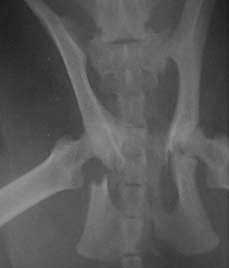

This is a radiograph of cat with a fractured pelvis that is more severe than the one Sundance has. Do you see the fracture on both sides?